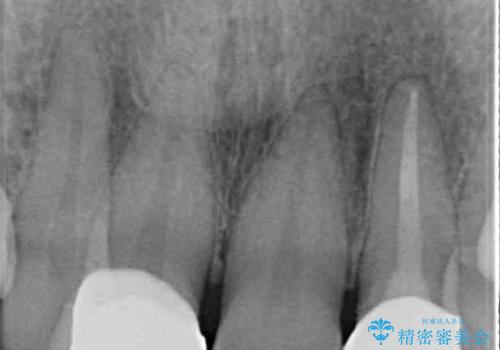

レントゲン写真より、歯根の炎症が認められなかったため、ファイバーコアによる土台築製後、オールセラミッククラウンにて補綴することとしました。